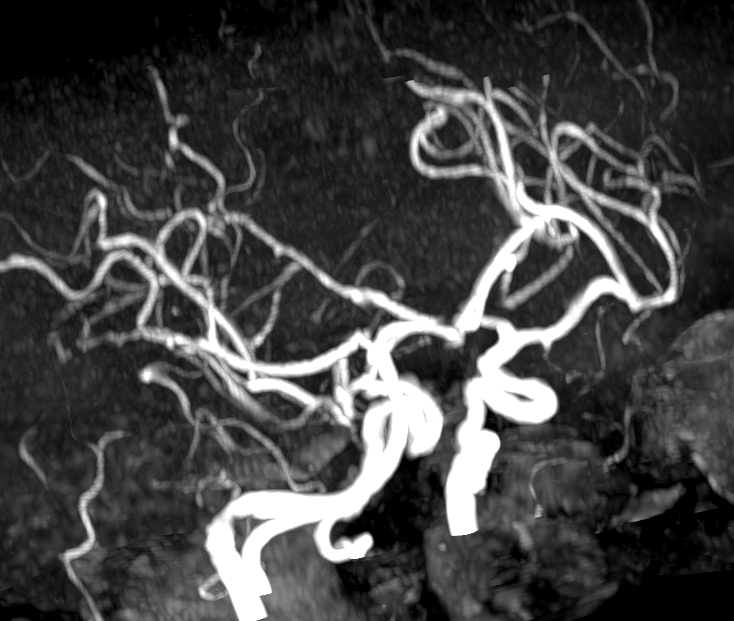

Показания для проведения МР бесконтрастной ангиографии артерий и вен головного мозга:

Как проводится МР бесконтрастная ангиография артерий и вен головного мозга?

Перед укладкой в томограф необходимо снять все металлические предметы. После этого пациент ложится на стол сканера, который постепенно перемещается в аппарат. Во время сканирования следует лежать неподвижно, чтобы получаемые изображения были четкими и неискаженными.

- высококачественные снимки органов и тканей;

- подробную расшифровку результатов;

- возможность детального разбора с участием врачебного консилиума.